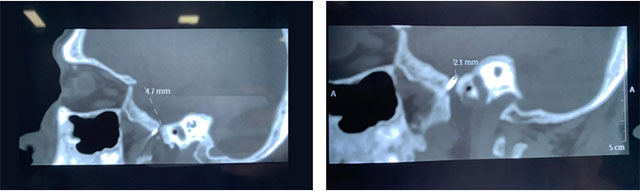

在明確告知手術(shù)風(fēng)險并由患者家屬簽字確認后,杜立功醫(yī)生在劉偉欽主任的協(xié)助下,為程老伯開展了微創(chuàng)治療;颊呔植柯樽頎顟B(tài)下,杜立功在CT引導(dǎo)下將射頻針穿刺進靶點,并一點點調(diào)整方向,穿刺進入患者左側(cè)半月節(jié)。通過一系列專業(yè)的電生理測試,選擇合適的點位進行多點治療。歷時半小時的治療后,患者的疼痛得到明顯緩解。術(shù)后一周,經(jīng)檢查程老伯身體狀況良好,三叉神經(jīng)痛未再發(fā)作。

杜立功醫(yī)生介紹,三叉神經(jīng)半月節(jié)射頻熱凝術(shù)是一種微創(chuàng)治療。手術(shù)采用CT、“C”形臂影像引導(dǎo)確保準(zhǔn)確穿刺卵圓孔和三叉神經(jīng)半月節(jié)。穿刺到位后用弱電流刺激三叉神經(jīng)半月節(jié),可驗證擬治療靶區(qū)與患者疼痛發(fā)作區(qū)是否吻合,使治療變得更加精細和安全。溫控?zé)崮窃谥委煱袇^(qū)逐步升溫,利用痛覺和觸覺神經(jīng)纖維對熱度的耐受力不同,選擇性治療痛覺神經(jīng)纖維,治療過程準(zhǔn)確可調(diào)控。